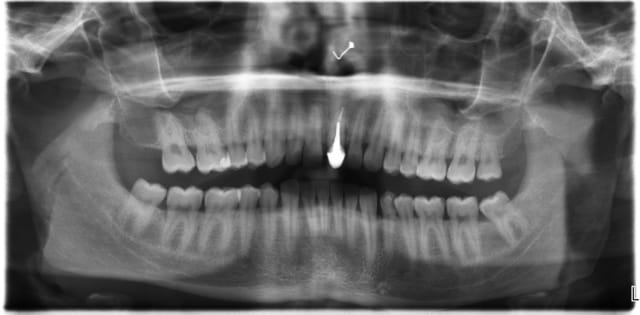

J'ai de tout en boutique..jeune homme 25 ans accident de piscine choc sur la bordure ( fêlure existante..fistule), extraction le jour même, temporisation 4 mois (avec un bout de trombone) Monobloc 16mm 60N, prep cap zircone droit 2/2 provisoire ion, temporisation 3 mois ceramo ceram..

J'ai de tout en boutique..jeune homme 25 ans accident de piscine choc sur la bordure ( fêlure existante..fistule), extraction le jour même, temporisation 4 mois (avec un bout de trombone) Monobloc 16mm 60N, prep cap zircone droit 2/2 provisoire ion, temporisation 3 mois ceramo ceram.. suite des photos :)

Au contraire..si tu regarde attentivement les radios tu veras qu'en quelques mois il y a une néoformation osseuse autour des micros spires. On voit un manque le jour de la pose et plus d'os avec la Procera. Volontairement j'ai pas plus enfoncé l'implant ..Si j'avais ouvert j'aurai bousillé tout le potentiel cicatriciel..Charon l'a démontré depuis longtemps en paro. Aux patient je leur explique que "Ouvrir c'est comme tondre le gazon avec un motoculteur" .

Donc il y maintien et renfort du parodonte.